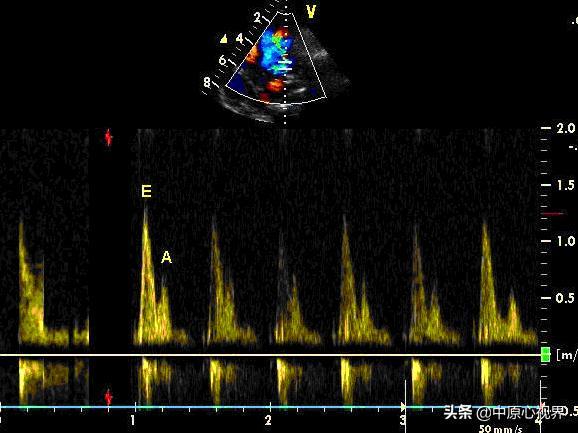

A峰和E峰是通过多普勒超声技术获得的二尖瓣口舒张期血流频谱中的两个重要参数。E峰代表舒张早期的最大峰值速度,而A峰则代表舒张晚期的最大峰值速度。这两个参数的变化可以反映左心室舒张功能的状态。

正常情况下,E峰和A峰的比值(E/A比)应在1.0到2.0之间。当左心室舒张功能减退时,E/A比会发生变化。在舒张功能轻度异常时,E/A比小于1.0;中度异常时,E/A比在1.0到2.0之间;重度异常时,E/A比大于2.0。